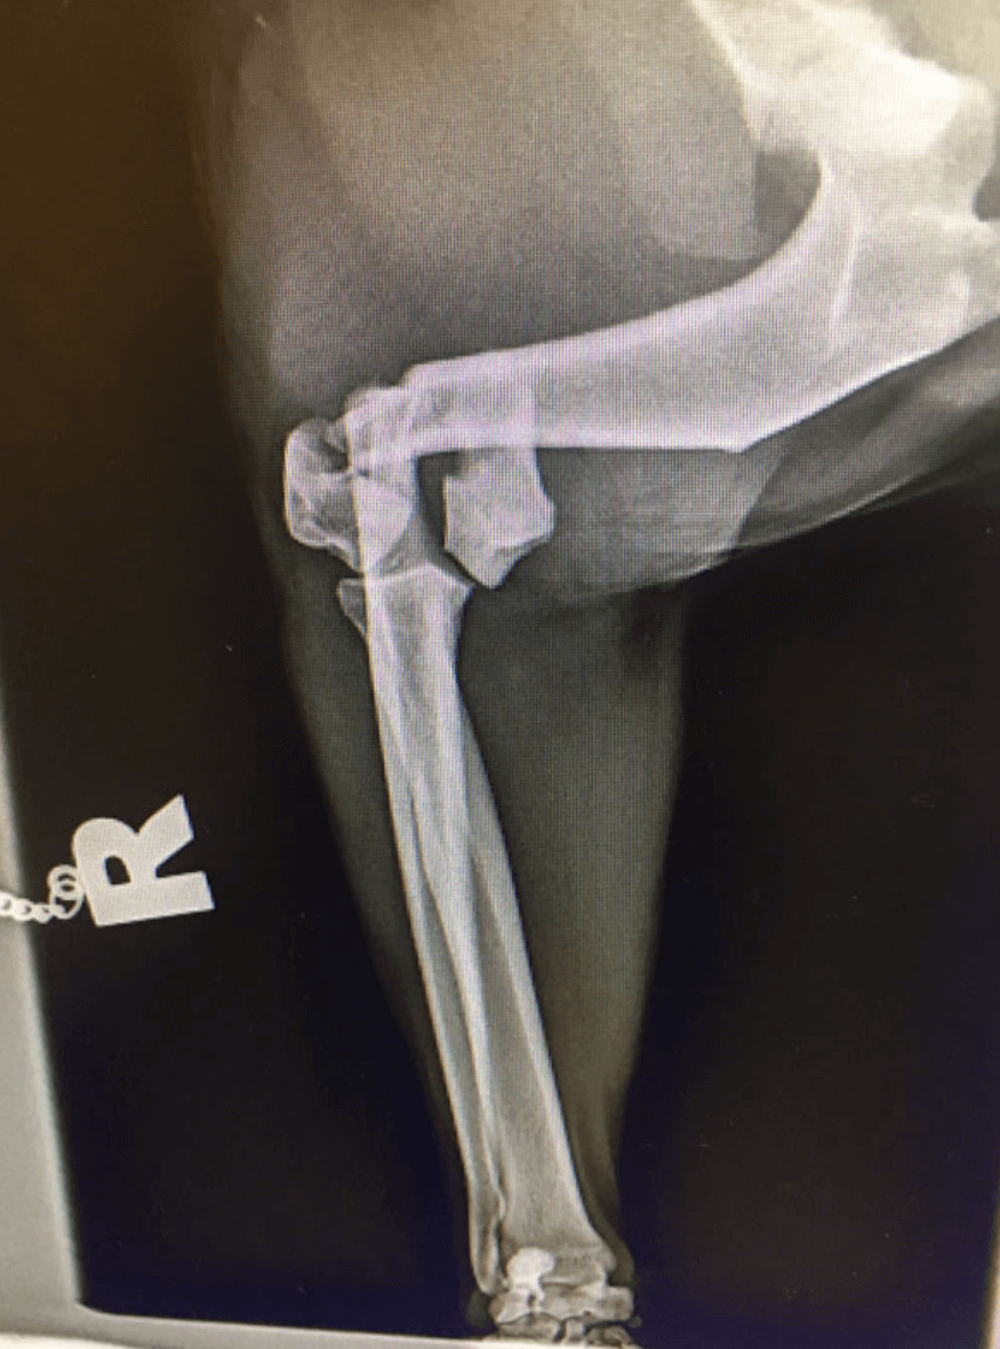

Radius and Ulna Fracture Repair

Example of Minimally Invasive Radius and Ulna Fracture Repair.